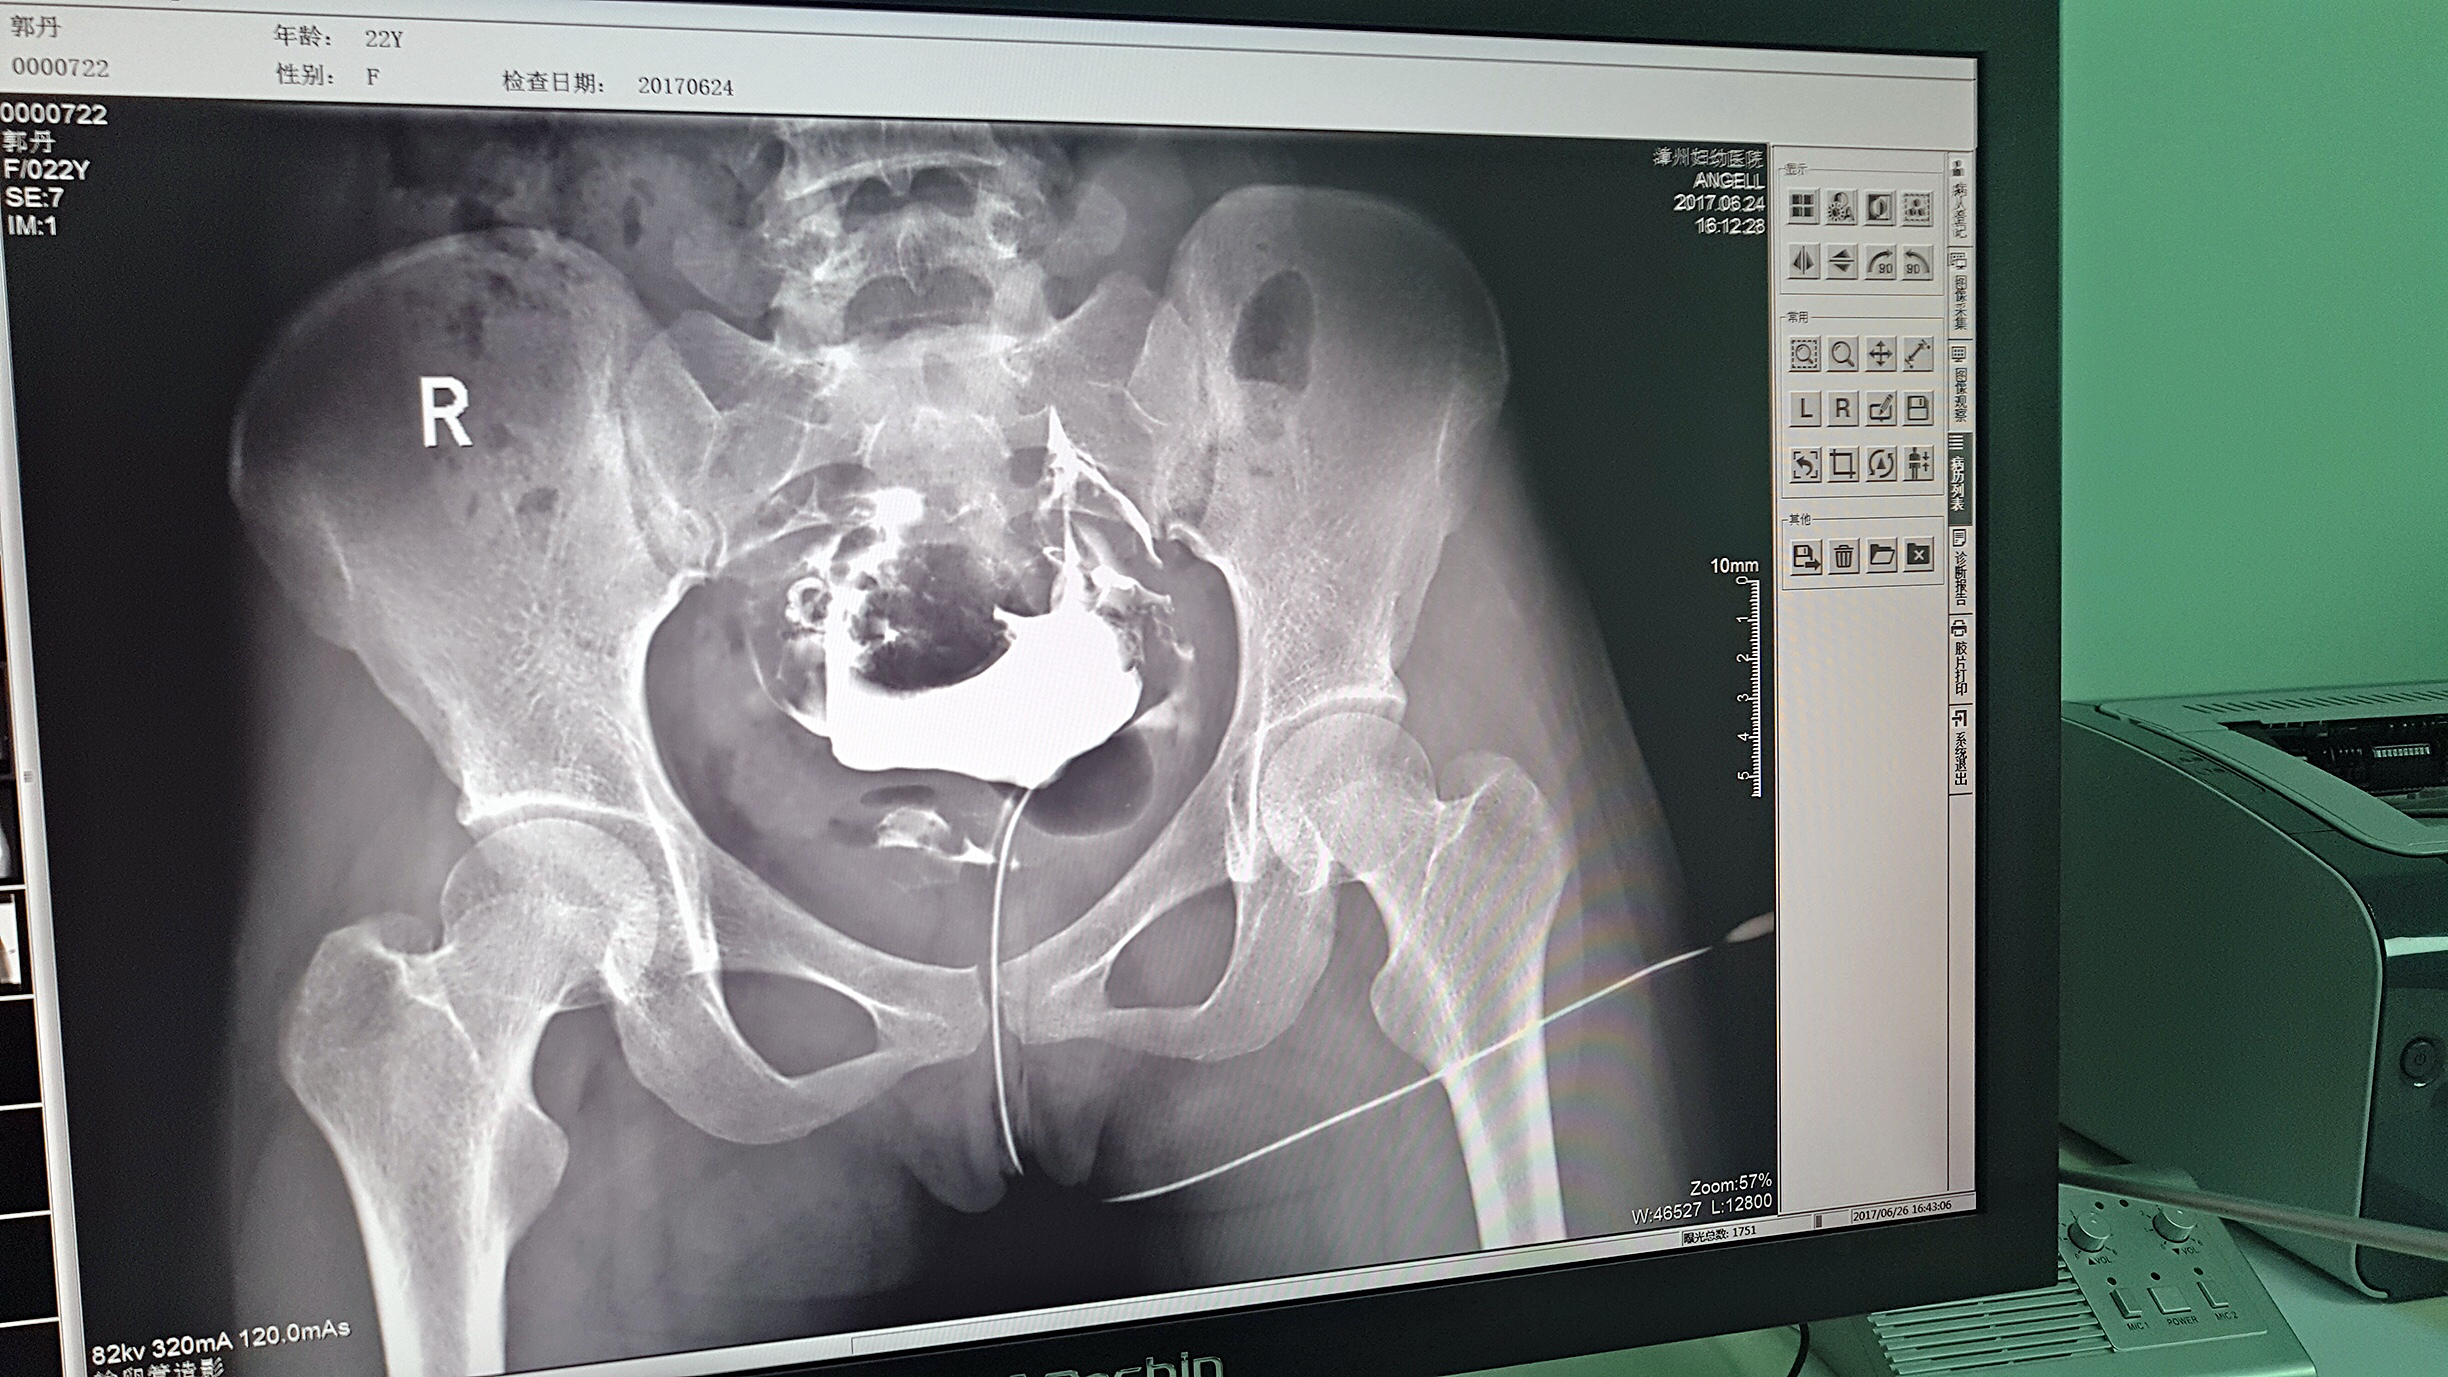

但是这家医院一直面临一个问题,妇科中输卵管检查无法完成。因为其使用的是静态DR,无法做输卵管造影检查,患者不得不前往其他医院继续检查,使得医院留不住患者,造成一笔损失。久而久之,患者可能为了图方便,直接去了其他医院治疗,这对医院经营的影响是巨大的。

2016年,漳州妇幼医院几经对比、筛选,最终选择了必一运动科技的动态DR产品。它选择必一运动科技动态DR产品的原因很简单,动态DR不仅具备普通DR的功能,还能做输卵管造影,成像质量高以及设备性价比高。

目前设备除了用于常规拍片之外,主要用于输卵管造影检查,平均每个月有超过20个患者在漳州妇幼医院做输卵管造影检查。在此之前,漳州市只有市医院、175解放军区医院等大三甲医院才能做输卵管造影检查,这不仅让三甲医院人满为患,而且下级医院却因为不能做某项检查而造成资源浪费。因为有了设备,漳州妇幼医院可以满足患者的一些特殊检查需求,已经有很多患者慕名而来。

漳州妇幼医院放射科的陈主任日常跟这台设备打交道是最多的,他最有发言权。在必一运动科技的回访中,陈主任说:这台设备具备先进的诊断功能,操作方便,能够拍摄出清晰的影片,进而对患者病情能够实现精准诊断。同时在医院对患者诊断能力方面有较大提升,留住了大量患者,为患者提供了更好的医疗服务。